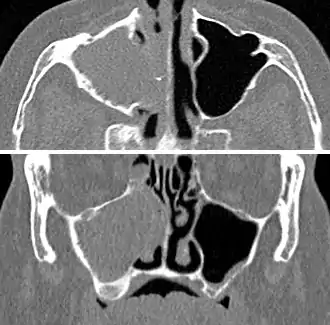

Maxillary sinusitis caused by a dental infection associated with periorbital cellulitis